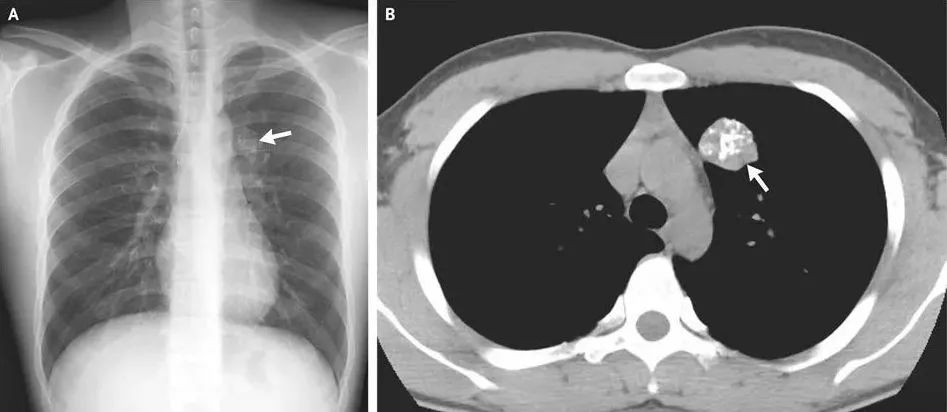

事实上,在X线片、 CT、钼靶、超声报告中,常常会出现“钙化”“钙化灶”的字样。据生命时报,钙化,指人体内的钙离子以磷酸盐或碳酸盐形式,发生沉积的过程。很多钙化是在人体病变修复过程中形成的,整个过程和伤口愈合结疤类似。通常表现为钙盐沉积在受损组织中,使这些组织变得坚硬。

肺部钙化:一般来说,肺部的单个或少量钙化灶多为陈旧性病变遗留,通常无需特殊治疗,定期复查观察即可。但如果钙化灶较大或数量较多,伴有其他异常表现,如咳嗽、咳痰、咯血、胸痛等,则需要进一步检查。